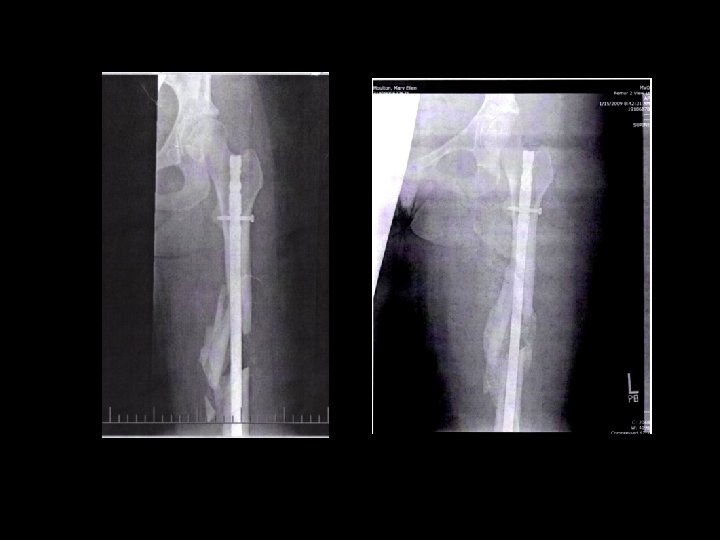

Internal Fixation